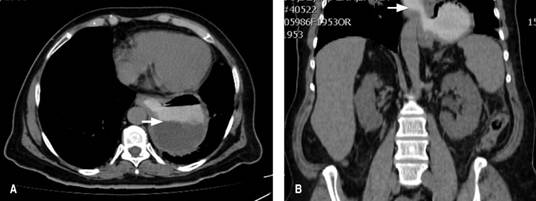

Fue valorada en el Servicio de Cirugía General, donde se inició el protocolo de estudio; se realizó una endoscopia de tubo digestivo alto, que demostró la presencia de un divertículo esofágico a 32 cm de la arcada dentaria superior, con alimento parcialmente digerido en su interior, con un diámetro aproximado de 5 cm, además de gastropatía crónica de predominio en el cuerpo y antro (Figura 1). Se complementó con una manometría esofágica en la cual se detectó hipertonía del esfínter esofágico inferior. Se realizó una tomografía axial computarizada (Figura 2), que demostró una imagen sacular paraesofágica en el tórax con nivel hidroaéreo en su interior.

Figura 2: Tomografía axial computarizada con contraste oral en corte axia l ( A) y coron al ( B), donde se observa la presencia de una imagen sacular paraesofágica, con presencia de material de contraste en su interior y que evidencia la presencia de nivel hidroaéreo en su interior (flecha).